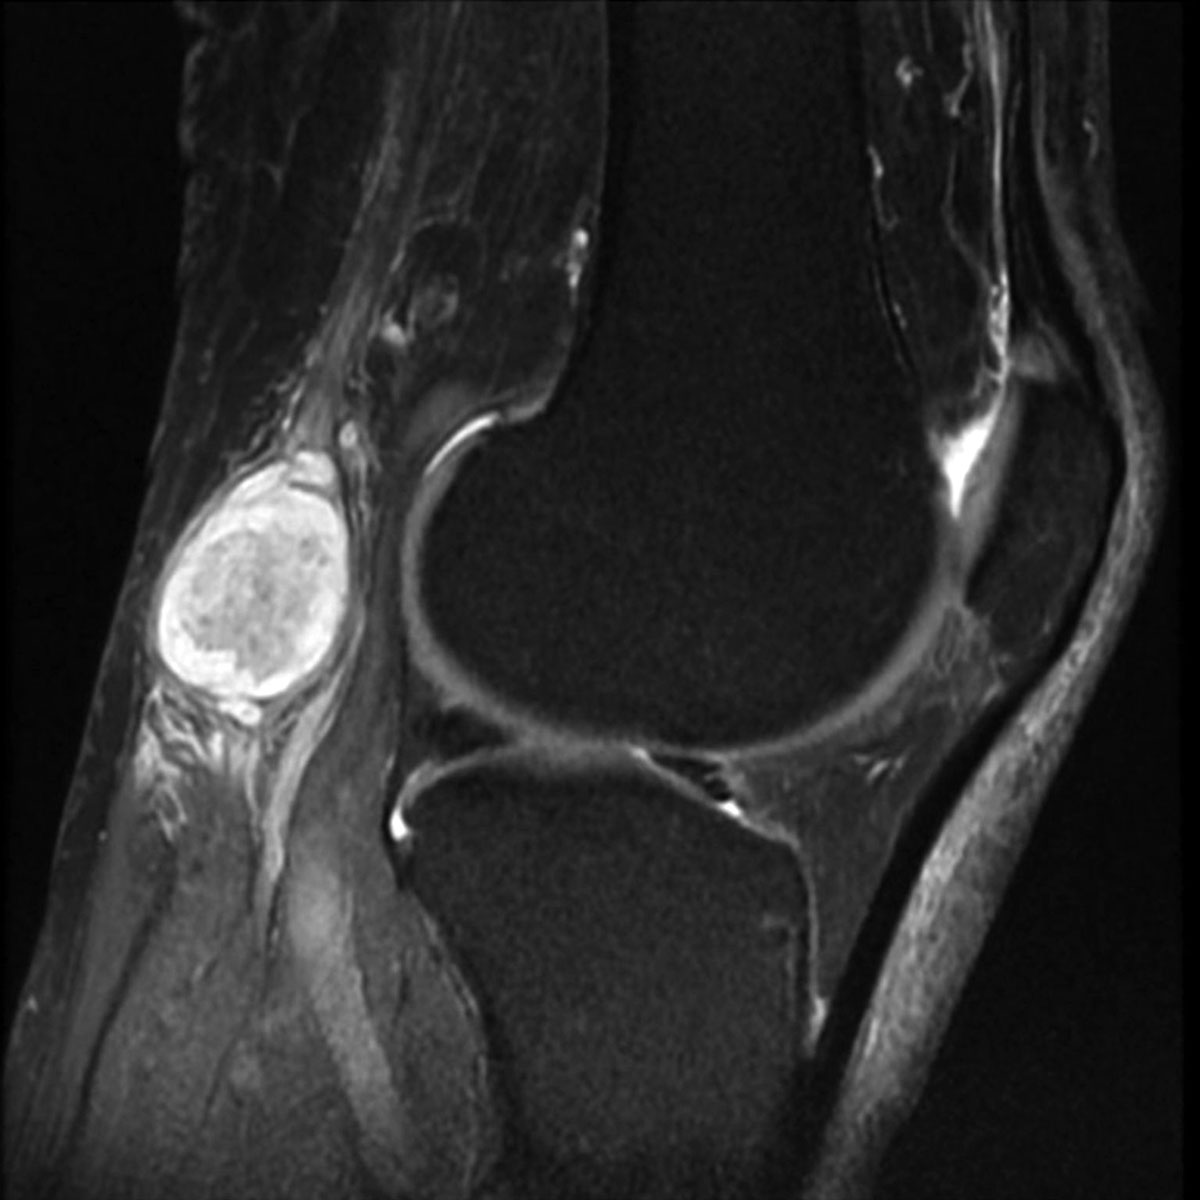

Для диагностики кисты Бейкера обычно используют магнитно-резонансную томографию (МРТ) и компьютерную томографию (КТ). Ультразвуковые исследования назначаются реже. Основная цель этих процедур — выявление аневризм, злокачественных образований и дегенеративных изменений. На основе полученных данных разрабатывается план лечения и составляется прогноз.